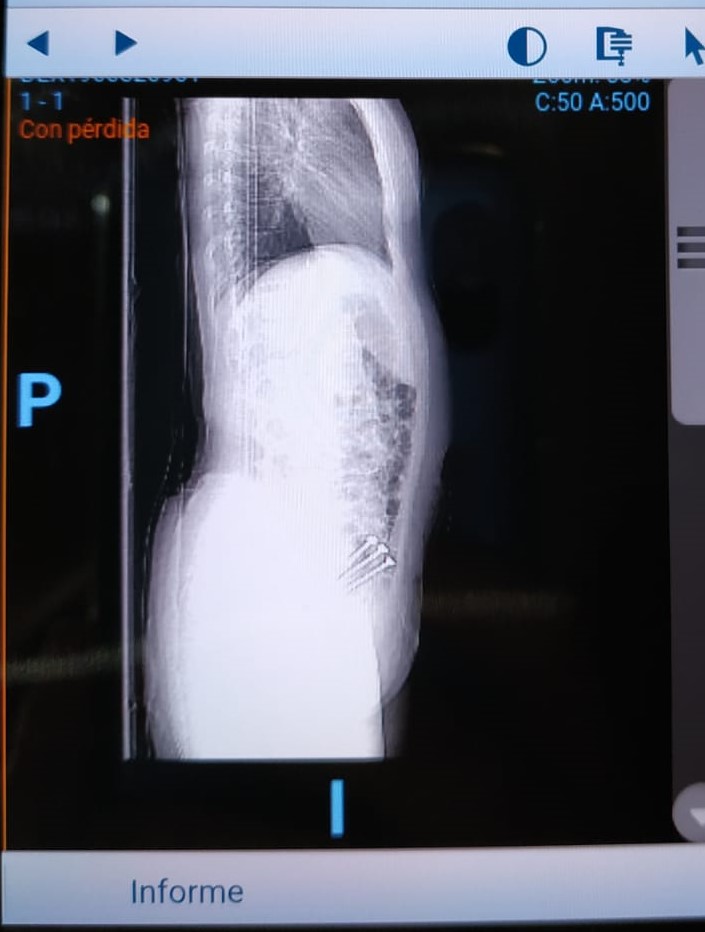

Decidieron hacerme una radiografía de medición de miembros y efectivamente, salía lo que pensábamos todos. Tengo una pierna un poco más larga que la otra. No es algo que se note a leguas, pero sí algo que me ha provocado un pinzamiento en la L4 y L5 y probablemente por lo que la primera operada, que es la pierna más corta, me duela.

Voy a dejaros por aquí las imágenes de la Rx.